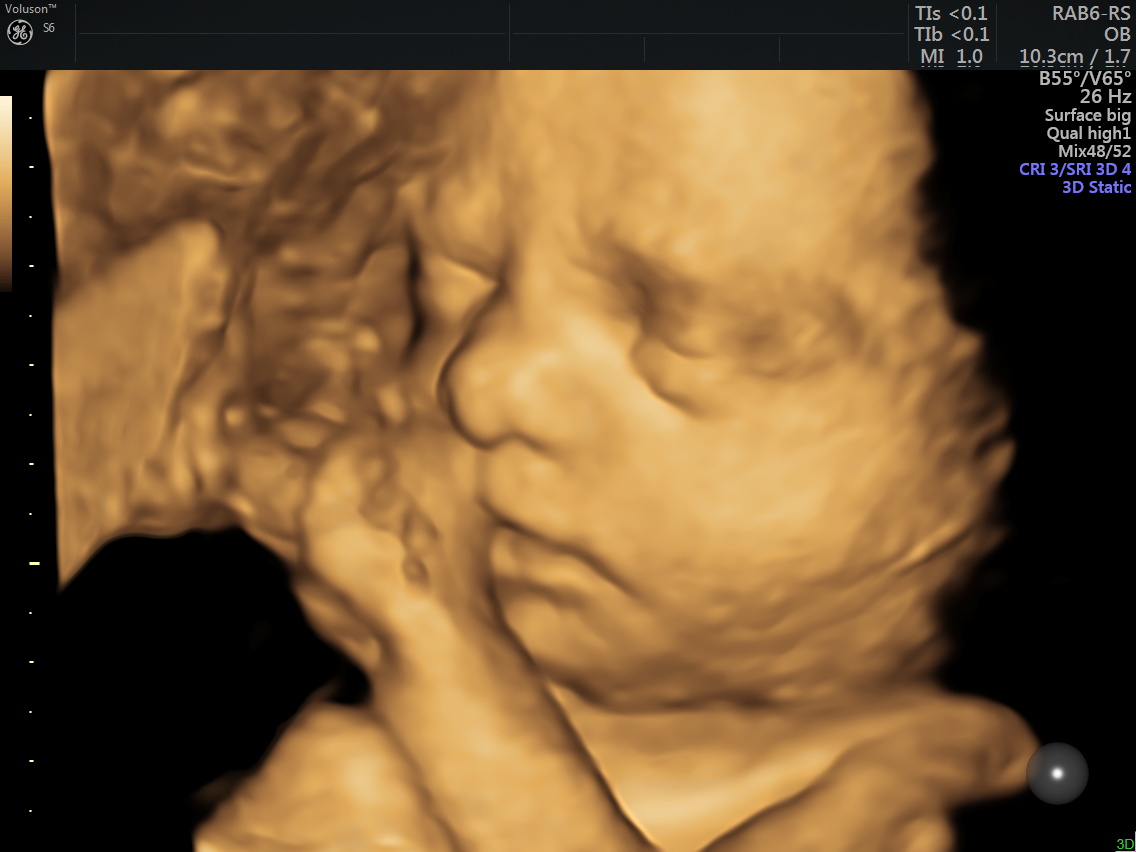

Anne adayı 4D Renkli Ultrason Sayesinde Bebeğine Daha Kolay Bağlanabilir.

4 boyutlu renkli ultrason cihazı ile çok erken dönemde cinsiyet, yarık dudak, yarık damak, eksik parmak, beyin ve omurilikten kaynaklanan rahatsızlıkların erken tanısı konulabiliyor.